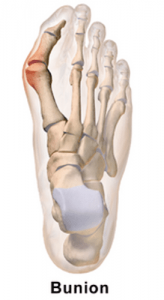

What is a bunion?

A bunion (also referred to as hallux valgus) is a condition described as a bump on the side of the big toe. The bunion occurs when the big toe starts to push against the 2nd toe. The bump that is seen on the side of the big toe is a mixture of an enlarged bone and dislocation of the big toe joint which is caused by the deviation of the metatarsal that changes the bony framework of the front of the foot.

Bunions come in a variety of shapes and sizes, from mild to severe, which is determined by their clinical appearance, physical examination and radiographic measurements. Depending on the severity of the bunion, the appropriate non-surgical or surgical approach can be determined.